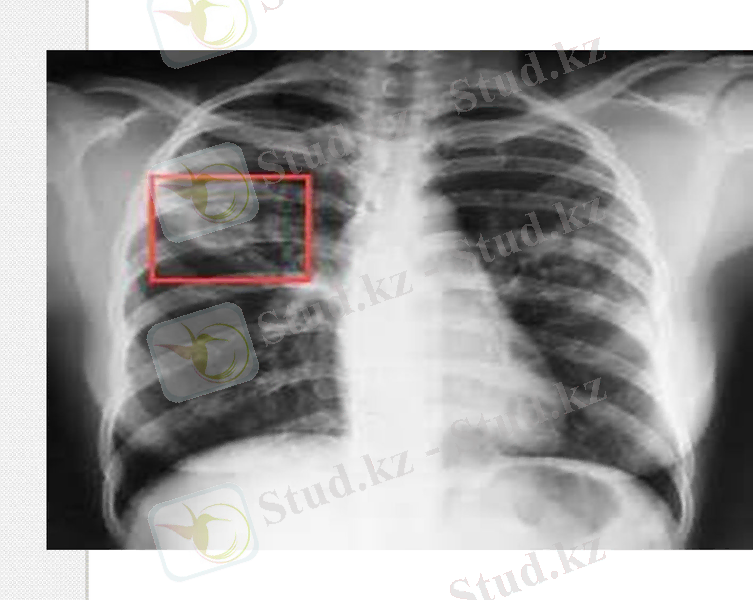

рентгенологиялық процесстер ретінде жаңа қабыну реакцияларының анық байқалған белгілері таралады:деструкцияның көптеген аймақтары мен және олардың екі беттік локализациясы. [14]

рентгенологиялық- инфильтриленген өзгерістердегі айқын білінбейтін өкпедегі шектелген процесстер, жалғыз каверналармен, кальцинаттар, рубец, өкпедегі фиброзды өзгерістер жиі байқалады, олар туберкулездік инфекцияның бастапқыдағы орын алмасуын дәлелдейді. [15]